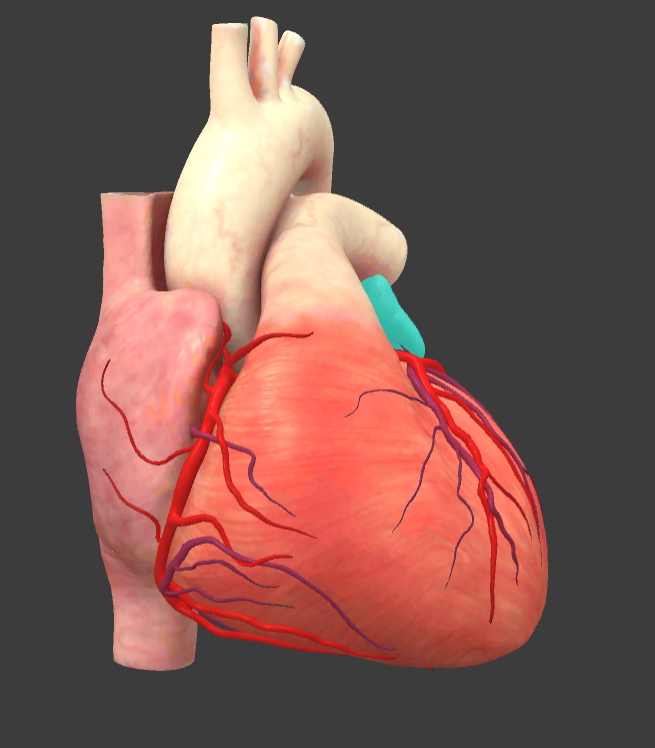

What is the name of the main vessels that supply the heart tissue with blood?

Coronary arteries

Left auricle

Pulmonary trunk

Right auricle

Right coronary a.